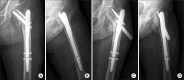

Methods: Eighty-two patients with intertrochanteric fractures that were treated with intramedullary hip nails between December, 2004 and January, 2011 were subjected to this study. The patients who could be followed for a minimum of one year postoperatively were enrolled. The immediate postoperative conditions were determined by radiograms: reduction status (3 parameters/4 points: contact accuracy of posteromedial cortex, severity of angulation, and distraction), fixation status (3 parameters/3 points: tip-apex distance, location of tip of the lag screw, entry point of the intramedullary nail), and fracture type (1 parameter/1 point: stable or unstable type by the Kyle's classification). Postoperative reduction loss and fixation failure were checked by radiograms taken at a minimum 3 months postoperative.

Results: Reduction loss and fixation failure were observed in 14 consecutive patients (17%). The fixation failure rate was 100% (2 patients) in score 1, 60% (3 out of the 5 patients) in score 2, 39% (3 out of the 8 patients) in score 3, and 50% (4 out of the 8 patients) in score 4 groups. There were fixation failures only in 1 out of 13 patients with score 5, and in 1 out of 18 patients with score 6. There was no fixation failure in 17 patients with score 7 and 11 patients with score 8.

Conclusions: Maintenance of the fracture reduction by the stable fixation in the patient scores over 5 could be predicted by the postoperative radiograms.